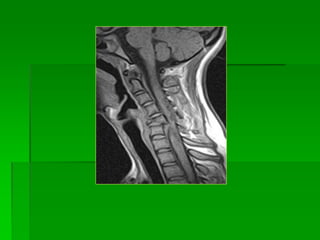

Bệnh nhân 35 tuổi đau lưng sau

chấn thương. MRI: TVĐĐ ngang

mức T11-12 và tổn thương tủy

tăng tín hiệu trên T2W, đứt dây

chằng dọc sau (mũi tên đỏ)